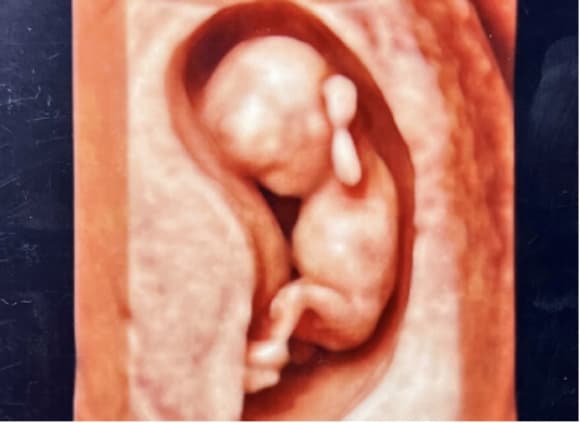

4D胎児エコー写真

4Dエコー外来

• 妊婦健診の中でいつでもご希望の時に、お腹の中の赤ちゃんの状態を立体的に、そして動きまでリアルにご覧いただける超音波技術を用いた4Dエコー外来が受診できます。

• お腹の中のお子さまの様子を鮮明にご覧いただくことが可能です。(希望者のみ:2,160円/回)

※当日の胎児の向きや、姿勢によって必ずしも顔がはっきり見られるとは限らないため、費用は見えたときのみいただいております。

(10週)

(12週)

(30週)

(36週)